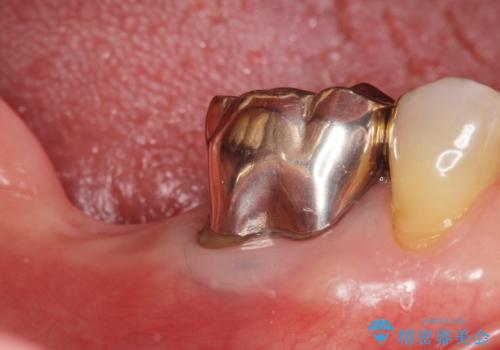

インプラントの種類:スプライン ツイスト (HAコーティング)

固定様式:セメント固定

クラウンの種類:オールセラミッククラウン スタンダード